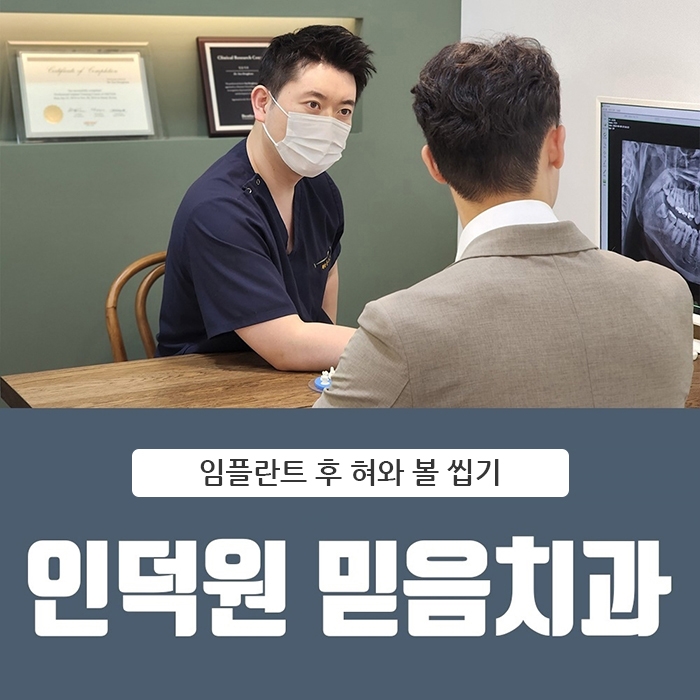

인덕원 임플란트 이후에 볼과 혀를 자주 씹어요

안녕하세요.

인덕원 믿음치과 원장 손동근입니다.

임플란트 치료를 받은 뒤

“요즘 자꾸 볼이나 혀를 씹게 돼요”라고 이야기하시는 분들이 생각보다 적지 않습니다.